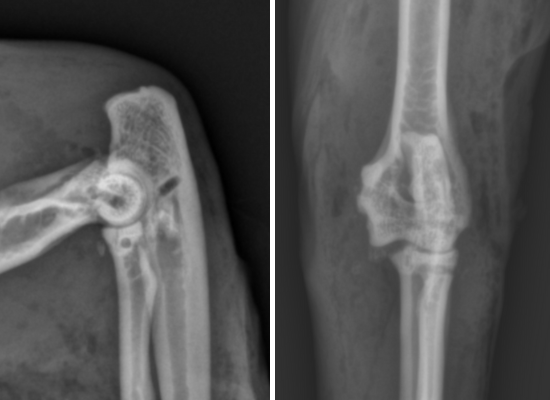

Le diagnostic repose sur des radiographies ciblées :

- Face : met en évidence le décalage latéral du radius et de l’ulna

- Profil : évalue la hauteur du déplacement et détecte d’éventuelles fractures

- Vues obliques : parfois nécessaires pour identifier une luxation latérale isolée

Ces examens servent aussi à planifier le traitement, conservateur ou chirurgical.

Traitement chirurgical

Recommandé en cas de luxation chronique, échec de la réduction ou fractures associées :

- Reconstruction des ligaments endommagés avec fils non résorbables

- Stabilisation articulaire par sutures circumférentielles ou techniques spécifiques

- Immobilisation post-opératoire similaire au traitement conservateur